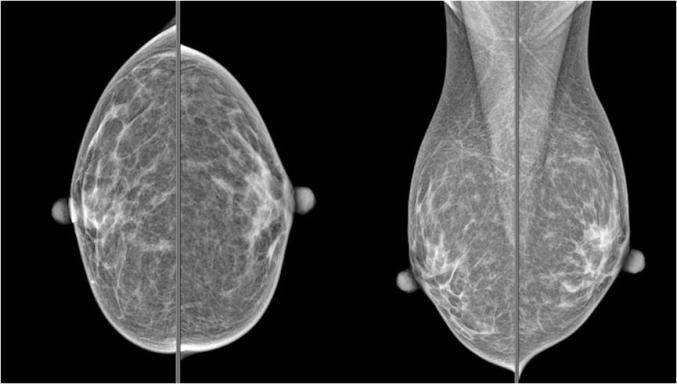

与常规X射线相比,乳腺钼靶采用了低能量的“软射线”。它的影像清晰度好、分辨率高,能显示乳腺各层次的结构和钙化,对乳腺软组织具有最佳影像效果更易发现微小病变,同时辐射更小,对人体伤害更轻微。

如上图所示,一次双侧乳腺钼靶检查共需要4次摄片,分别是左右双侧的正位和斜位。